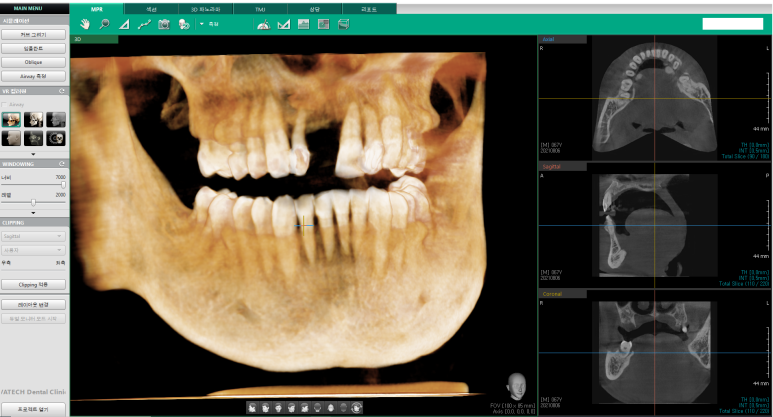

저희 치과에서 찍은 3차원 치과CT사진입니다.

앞니의 경우 어금니의 경우보다 주변 뼈가 얇아

임플란트의 각도가 중요하기 때문에

더욱 정확한 임프란트를 위해 네비게이션임플란트로 진행하였습니다.